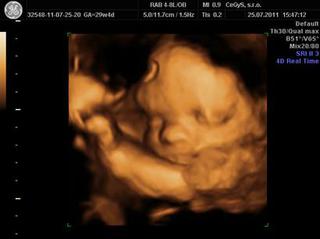

ahojte....konecne vam mozem ukazat malu z 3D /25.7./......mam jednu jedinu fotku, lebo ani v 20tt sa nechcela ukazat, ani teraz

@zuzanazuzana super fotecka, zda sa ze sa malicka uz krasne zagulacuje, uzasne ako mame v bruskach uz skoro hotove babatka 🙂

@zuzanazuzana velmi pekne fotecka, tieto 3D ultrazvuky su uplne skvele, clovek tak nmoze vidiet svoje babatko uz pred porodom 🙂))

@zuzanazuzana krásna fotočka 🙂